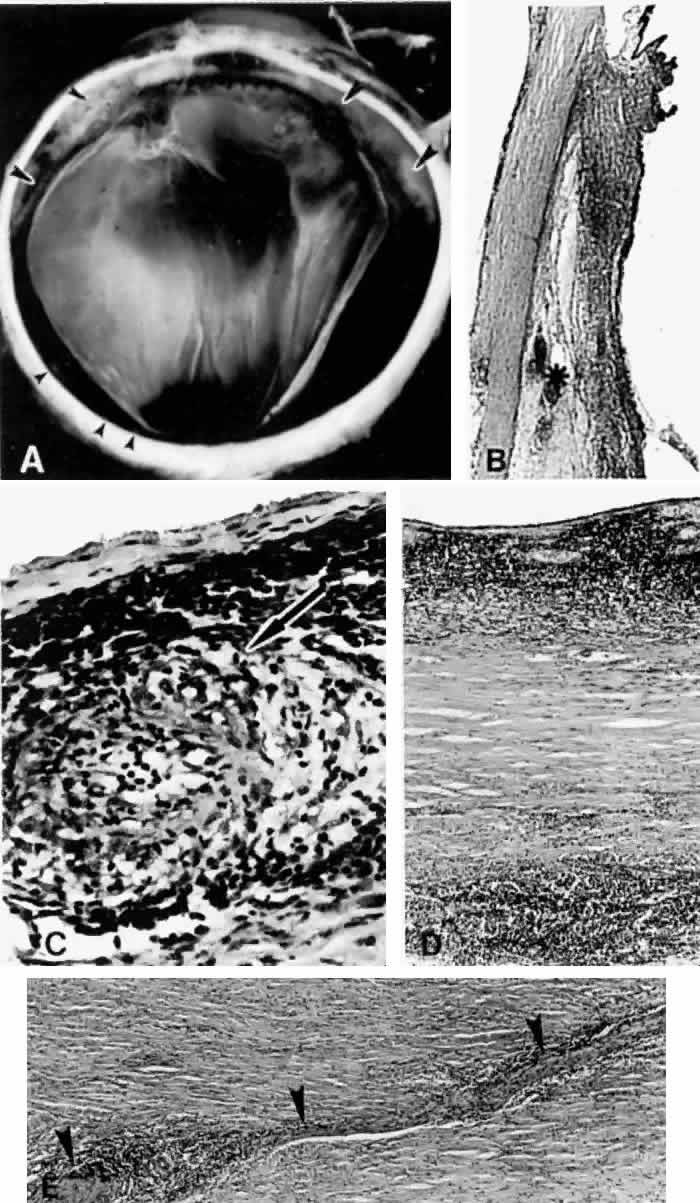

Fig. 8. This choroidal and ciliary body detachment, which occurred after intracapsular cataract extraction, was mistaken for a malignant melanoma.39 A. Iris incarceration in the wound (arrow) and extensive ciliary body effusion consisting of a dense, proteinaceous material (asterisk) (H & E, × 115). B. Effusion of the choroid near the ora serrata by a moderately dense, proteinaceous material without inflammatory cells. Note folds of choroid (arrowheads) (H & E, × 115).

Fig. 9. A. This serosanguineous ciliochoroidal effusion (arrow), which occurred after iridectomy for an iris melanoma in a 68-year-old man, was mistaken for a choroidal melanoma (H & E, × 25). B. Site of the limbal wound (arrowhead) with incarceration of the iris base and residual melanoma in the iris, anterior aspect of the ciliary body, and trabecular meshwork (H & E, × 60).

Fig. 10. A. This extensive ciliochoroidal effusion (asterisk), which occurred 4 years after iridencleisis in a 70-year-old man,39 was mistaken for a malignant melanoma. The iris (arrow) is incarcerated in the limbal wound, and a flat, edematous infiltration bleb (arrowheads) is present (H & E, × 25). B. Area of the ora serrata shows a ciliochoroidal effusion with proteinaceous material separating the tangentially oriented collagen fibers (arrowheads) that connect the choroid and ciliary body to the sclera (H & E, × 115).